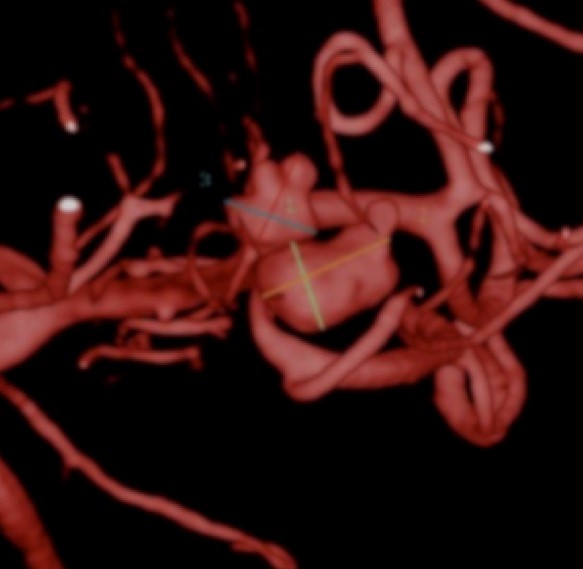

Fig. 3. Angiografia digital 3D: Aneurisma sacular pequeño bilobulado, con pseudoaneurisma asociado, responsable del sangrado.

Fig. 4. Angiografia digital 3D: Aneurisma sacular pequeño bilobulado, con pseudoaneurisma asociado, responsable del sangrado.

Fig. 5. Angiografia digital con substracción: Aneurisma sacular pequeño bilobulado, con pseudoaneurisma asociado, responsable del sangrado, a nivel de la bifurcación de la arteria cerebral media izquierda.

La distribución del diámetro mayor del aneurisma responsable de sangrado, la mayoría fueron pequeños menores a los 10 mm de diámetro, 7 aneurismas menores a los 5 mm, de los cuales 5 eran menores a los 2 mm de diámetro; 2 grandes menores de los 25 mm de diámetro y solo uno gigante mayor a los 25 mm de diámetro. (ver Diagrama 14).